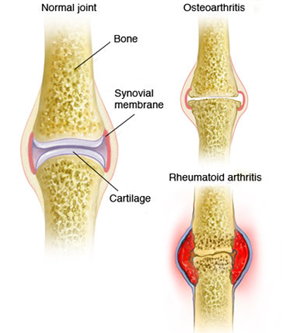

مفصل جایی است که دو استخوان بهم میپیوندند. انتهای این استخوانها با بافت محافظی به نام غضروف پوشانده شده است. آرتروز سبب تجزیه این غضروف میشود و باعث می شود استخوانهای مفصل به هم ساییده شوند. این مسئله میتواند باعث درد، سفتی و سایر علائم شود.

آرتروز در مقابل روماتیسم مفصلی

آرتروز یک عارضه حاد شونده و ناشی از فرسایش است در حالی که آرتریت روماتوئید یا روماتیسم مفصلی یک بیماری خودایمنی محسوب میشود و اگرچه در نهایت هر دو به التهاب مفصلی منجر میشوند اما عامل بوجود آورنده آنها متفاوت است. هر یک از انواع آرتریت علائم خاص خود را دارد. آرتریت روماتوئید بیماری فراگیری است به این مفهوم که تمام بدن را میتواند درگیر کند و آسیب ناشی از آن تنها به مفصلها محدود نمیشود. علائم اولیه آن نیز شامل تب پایین (در کودکان)، درد ماهیچه و خستگی بیش از حد است. این در حالی است که در مبتلایان به استئوآرتریت، علائم بیماری در تمام بدن بروز نمیکند و تنها به مفصلها آسیب میرساند. در حال حاضر بیش از 100 نوع آرتریت شناخته شده است كه شایعترین انواع آنها اوستئوآرتریت، آرتریت روماتوئید و نقرس هستند. در واقع هر نوع التهاب مفصلی شكلی از آرتریت محسوب میشود.

آرتریت روماتوئید (روماتیسم مفصلی)

آرتریت التهاب مفاصل است. این عارضه اغلب با درد، تورم، سفتی و حرارت در مفاصل آسیب دیده همراه است. آرتریت ممكن است با تعدادی از ناراحتیها و بیماری هایی مثل آسیب دیدگی، عفونت، اختلالات متابولیكی، یك سیستم ایمنی فوق العاده فعال و حتی مشكلات ناشی از وزن اشتباه گرفته شود.

آرتریت در واقع به بیش از 100 نوع مشكل روماتیكی اطلاق میشود كه مفاصل، ماهیچهها، تاندونها و حتی پوست و اعضای داخلی خاصی را تحت تاثیر قرار میدهد. شایعترین انواع آنها استئوآرتریت، آرتریت روماتوئید و نقرس هستند. در واقع هر نوع التهاب مفصلی شكلی از آرتریت محسوب میشود. تشخیص آرتریت بر اساس تستهای خون و رادیولوژی صورت میگیرد. این در حالی است كه آرتروز عمدتا ناشی از افزایش سن است و اساسا غضروفها را دچار میسازد. این آسیب غضروفی سبب بروز درد، كاهش توان حركت و كاهش توان ماهیچهای میشود. اما باید بدانید كه فعالیت و ورزش منظم میتواند غضروفها را تغذیه كند.

آرتریت روماتوئید کل بدن را تحت تاثیر قرار میدهد. بیماری خودایمنی هنگامی رخ میدهد که دستگاه ایمنی بدن به اشتباه حمله به خودِ بدن را آغاز میکند. علائم این بیماری میتواند شامل خستگی شدید و گرفتگی عضلات به هنگام صبح و همچنین درد مفاصل باشد.

بدنِ مبتلایان به این بیماری، بافت نرم و جداری اطراف مفاصل موسوم به «غشاء سینوویوم» را همچون ویروس و باکتریِ خطرزا تلقی کرده و به آنها حمله میکند. «غشاء سینوویوم» وظیفه حفاظت از مفاصل و نرم نگه داشتن آنها را به عهده دارد. این حمله موجب میشود مایعی در مفصل جمع شود. انباشت این مایع موجب ورم، درد، گرفتگی عضلات و التهاب اطراف مفصل میشود. این وضعیت در نهایت به فرسوده شدن مفاصل منجر میشود.

آرتروز هنگامی رخ میدهد که غضروفهایی که انتهای استخوانهای مفاصل شما را پوشش میدهند به تدریج خراب شوند. غضروف یک بافت سفت و لغزنده است که حرکت مفصلی تقریباً بدون اصطکاک را امکانپذیر میکند. در نهایت، اگر غضروف کاملاً فرسوده شود، استخوان روی استخوان ساییده میشود.

آرتروز غالباً به عنوان بیماری “سایش” شناخته میشود. اما علاوه بر تجزیه غضروف، آرتروز کل مفصل را تحت تأثیر قرار میدهد؛ باعث ایجاد تغییراتی در استخوان و تحلیل رفتن بافتهای پیوندی مفصل شده و عضله را به استخوان متصل میکند. همچنین باعث التهاب پوشش مفصلی میشود.